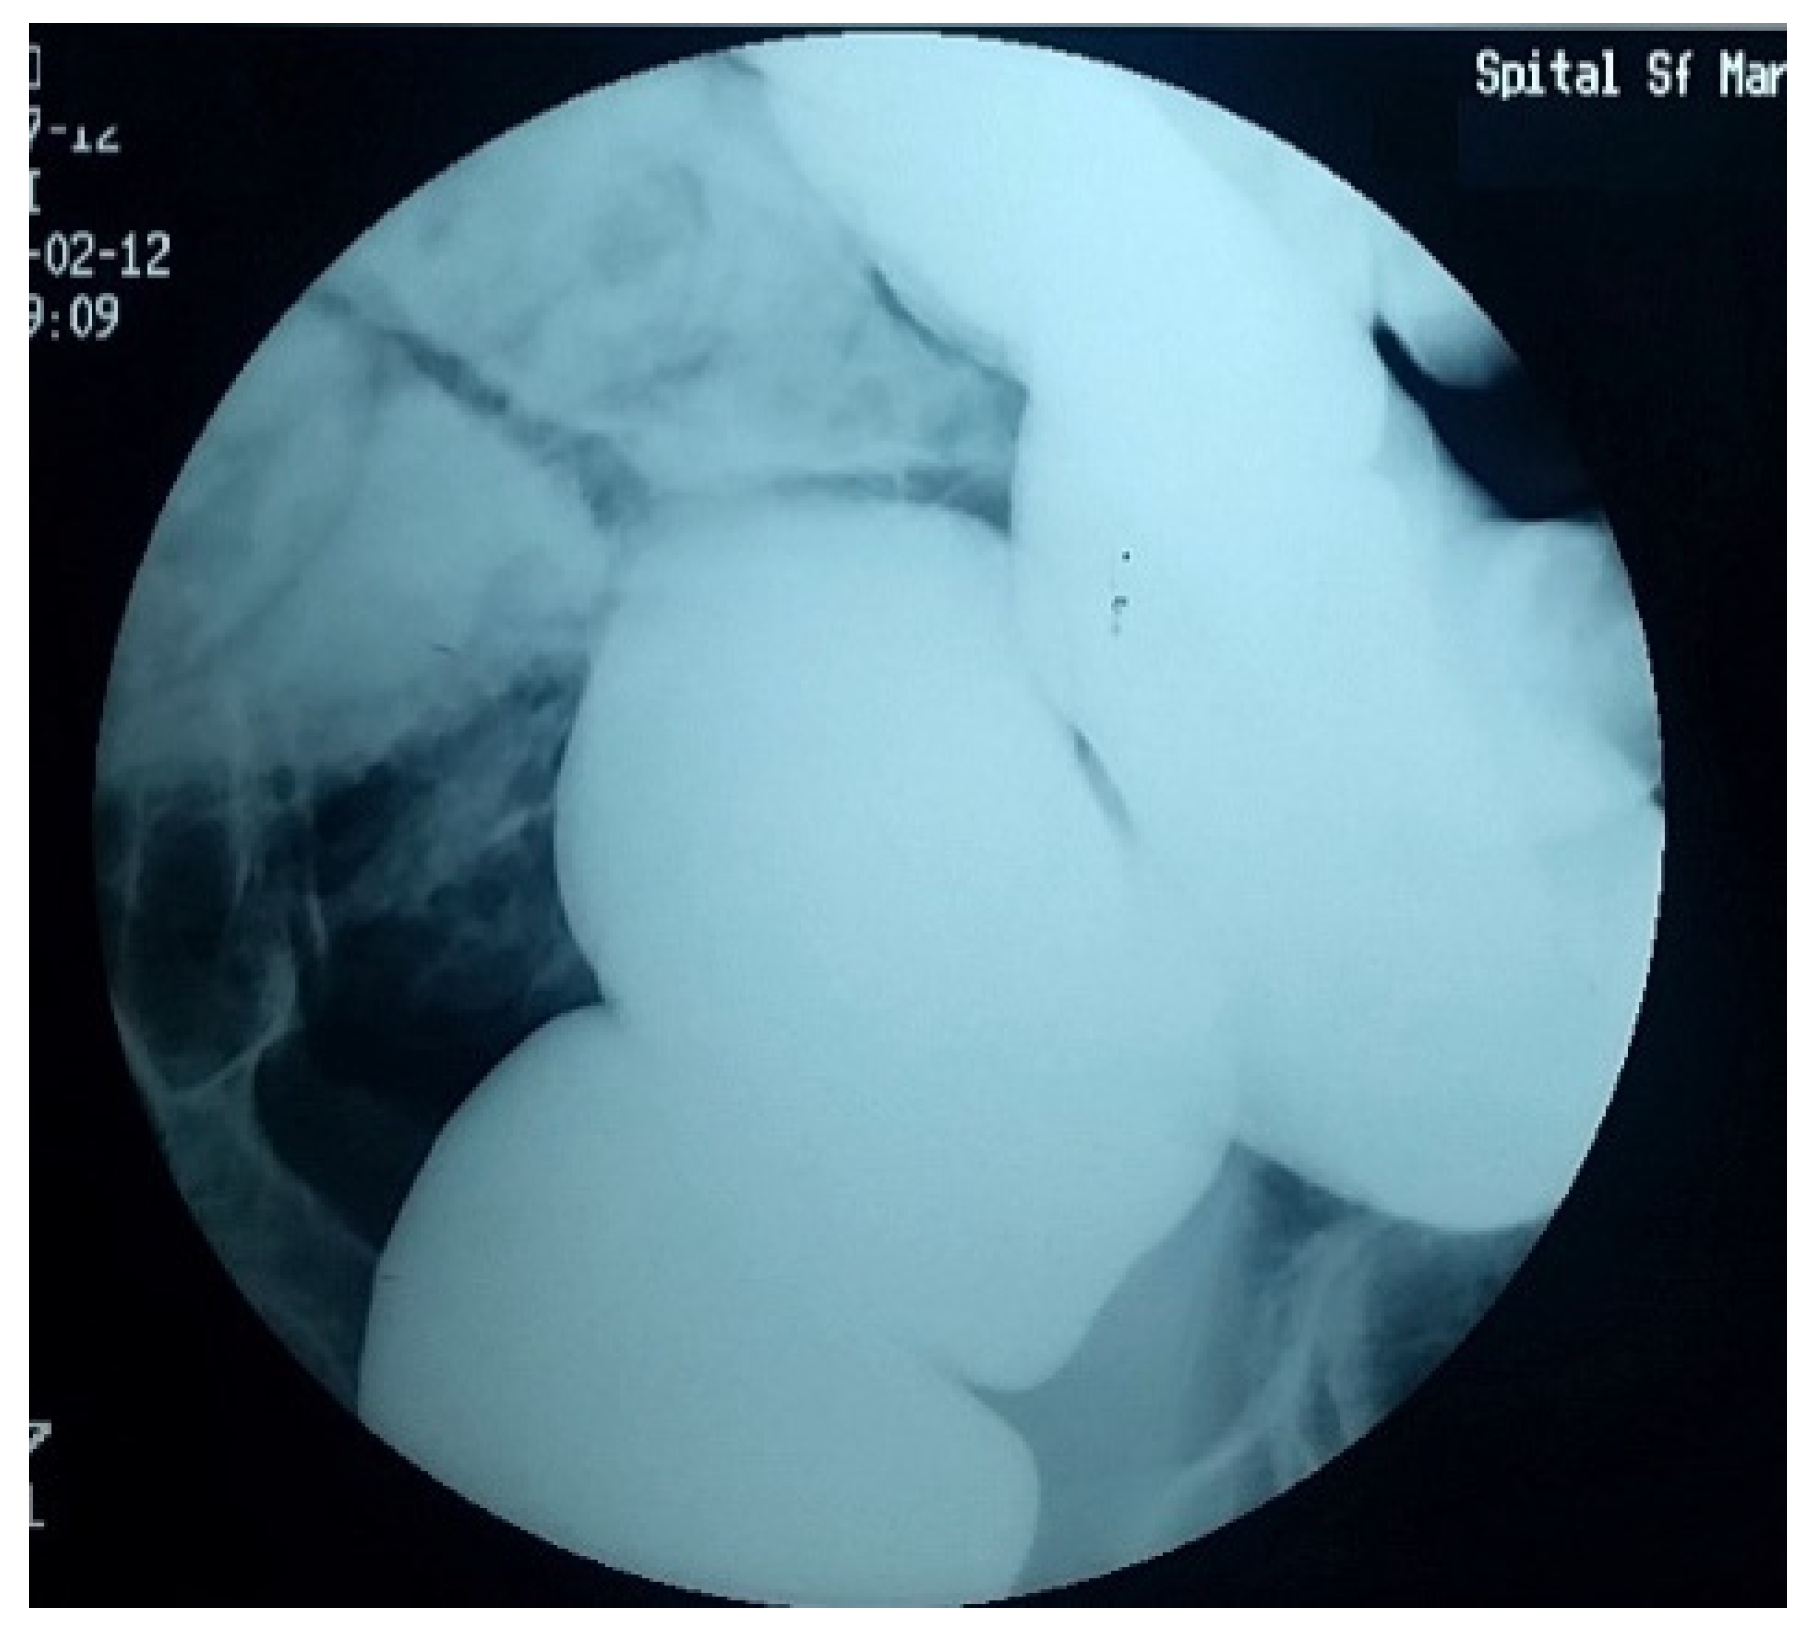

4. Diagnostic Criteria for the Acquired Megacolon